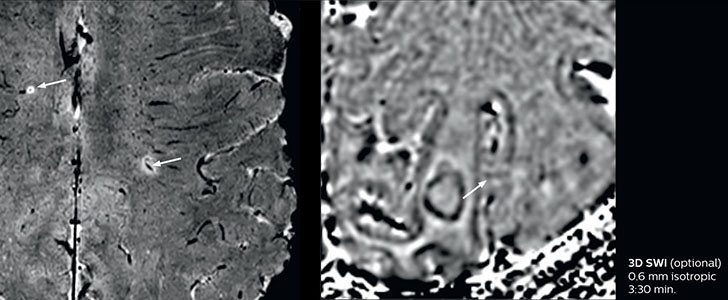

Fast MS protocol with optional sequences

The abbreviated MS protocol for brain is only around 9 minutes, so in case of suspected multiple sclerosis, one or two more advanced sequences may be added, such as PSIR (phase sensitive inversion recovery) or susceptibility-weighted sequences to help us make more confident diagnoses in these inflammatory cases.

In this example, the optional 3D multishot susceptibility weighted sequence with 0.6 mm isotropic voxels is 2 lesions with a central vein sign (arrows) and one lesion with a phase-rim sign (arrowhead). The total scan time, including SmartBrain and axial PD/T2 3mm, is 11:10 min. and is 18:30 min. with the optional 3D PSIR and 3D SWI multishot included.

3D TFE T1

3D FLAIR

DWI image

3D T1w TSE Gd

3D PSIR

3D SWI

“In multiple sclerosis patients, we increasingly include a multishot susceptibility sequence [3] in our routine cases, thanks to the shorter scan times. Our abbreviated MS protocol for brain is around 8 to 9 minutes, so we can ask for one or two additional sequences to visualize the central veins, or to get an additional contrast to better depict posterior fossa lesions. In cases of white matter lesions of unknown significance on FLAIR images, for example when we see high signal hyperintensities in the brain, we can add on more advanced sequences such as PSIR (phase sensitive inversion recovery) or susceptibility-weighted sequences to help us in distinguishing between MS and nonspecific or vascular abnormalities in these inflammatory cases.”